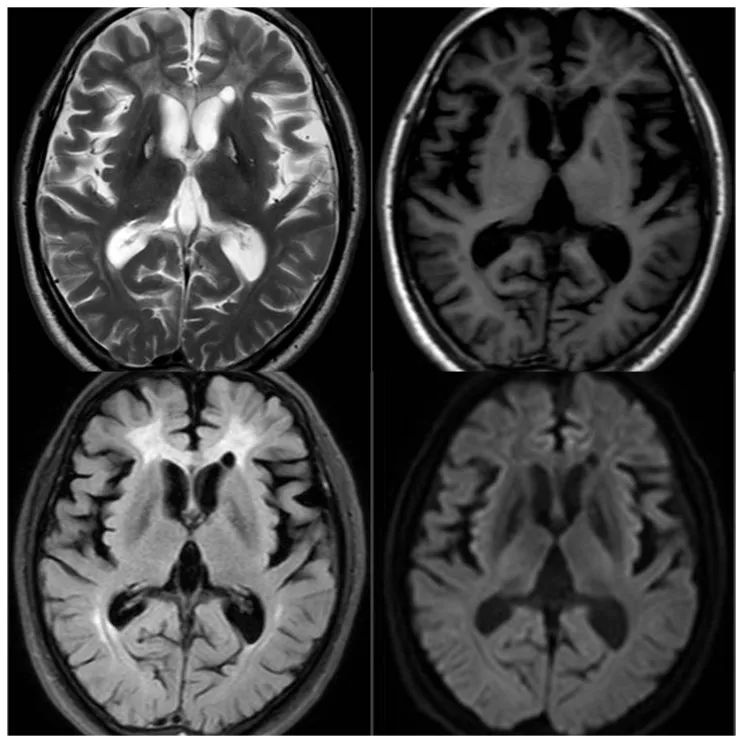

男,55 岁,主因 「 一氧化碳中毒 46 天,记忆力减退 7 天。于 46 天前在旅馆住宿时吸入煤烟后出现意识不清,有大小便失禁,次日早晨被人发现送至当地医院,明确诊断为 「 一氧化碳中毒 」,高压氧治疗 1 次后,当日意识转清,之后继续在当地医院住院治疗,共行高压氧治疗 25 次(压力 2.0ATA,前 3 日每日两次,后每日一次连续 19 天)后好转出院。7 天前患者出现记忆力减退,以近记忆力减退为主,时有胡言乱语。

影像学表现为双侧苍白球及侧脑室周围白质对称分布异常信号,皮层下 U 型纤维未受累。